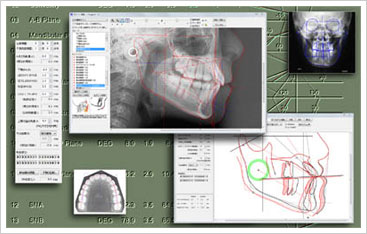

当院では、矯正治療の診断機材として、コンピューターシミュレーションソフト(COA5)を導入しております。

患者様にとって残念なことは「せっかく治療したのにイメージした歯並びと違う」ということです。そうならないために、当院では、治療を行う前に患者様の「理想」をお伺いした上で、シミュレーションソフトにて完成イメージをお見せしています。

この工程を踏むことで「自分の歯並びがどのように変わるのか」「望みどおりに本当にキレイな歯並びになるのか」を事前に把握できますし、何よりも、治療後のイメージを患者様そしてドクターがしっかり把握した上で治療を進められますので「ズレ」をなくすことが可能になります。

この工程を踏むことで「自分の歯並びがどのように変わるのか」「望みどおりに本当にキレイな歯並びになるのか」を事前に把握できますし、何よりも、治療後のイメージを患者様そしてドクターがしっかり把握した上で治療を進められますので「ズレ」をなくすことが可能になります。

明確な目標をもって治療を始めることができるので、患者様にも好評です。